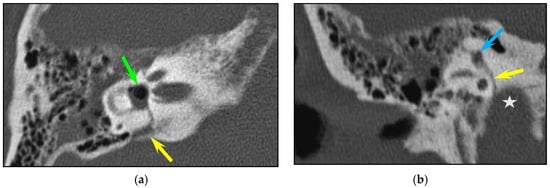

Longitudinal fractures were the most frequent pattern (88/126, 69.4%), followed by transverse (13/126, 10.3%) and complex (25/126, 19.8%) types. Only six fractures (6/126, 4.8%) showed involvement of the otic capsule. In one case, there was no visible fracture line but only pneumolabyrinth (in the vestibule and in the superior semi-circular canal). Three patients had a combination of fracture line and pneumolabyrinth (pneumovestibule: n = 3; air in semi-circular canals (n = 2) (Figure 1)).

In total, fractures involved the bony labyrinth in 11 cases and extended into the following structures: semi-circular canals (posterior semi-circular canal, n = 3; superior semi-circular canal, n = 2), vestibule (n = 3), cochlea (n = 1) and the vestibular aqueduct (n = 2). Involvement of the internal auditory canal was seen in two cases. Fracture lines extended into the petrous apex in 10/126 (7.9%) of all temporal bone fractures, and fractures along the osseous structures surrounding the facial nerve were seen in 8/126 (6.3%) cases. The fractures lines involved the geniculate fossa in four cases (Figure 2), the facial nerve canal in the tympanic cavity in two cases and the bony structure surrounding the second genu of the facial nerve in two cases, respectively. Air in the tympanic facial canal without a visible fracture line was present in one case.

Figure 1. Inner ear injuries. A transverse fracture in an 84-year-old woman with otorrhagia after a fall. CT of the right temporal bone; (a) axial plane; (b) coronal plane. (a) Axial plane: The fracture line extends inferiorly from the aqueduct of the vestibule (yellow arrow) to the vestibule, with associated pneumolabyrinth (green arrow). (b) The fracture line (yellow arrow) also involves the jugular foramen (asterisk) and the superior semicircular canal (blue arrow).